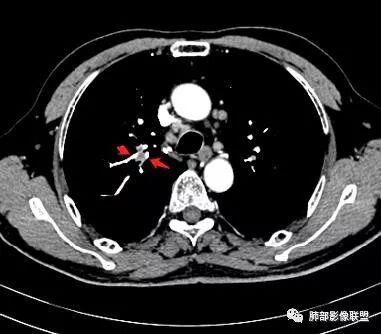

住院4天后行胸部增强CT

动脉期